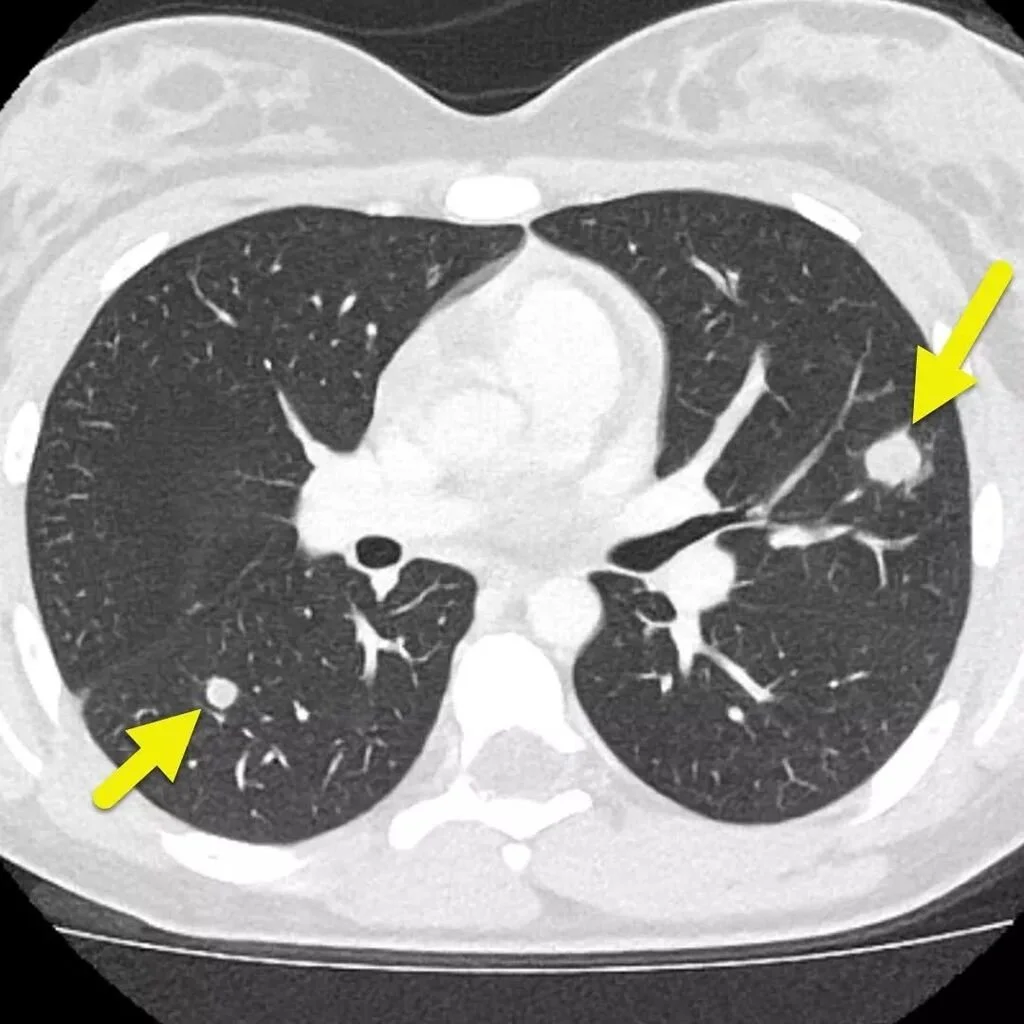

A pulmonary nodule (also known as a lung nodule) is a small, round or oval spot in the lung, typically measuring less than 3 cm, seen on a CT scan or chest X-ray.

• Appear as dense, well-defined lesions on CT

• Most common type

• Can be benign (e.g. scar tissue, granuloma) or malignant

• Risk depends on size, margins, and growth over time